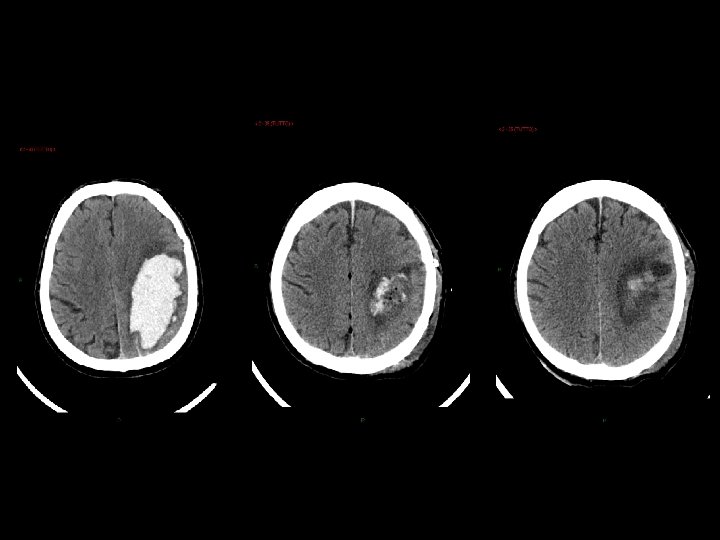

Stato vegetativo • giace, apparentemente incosciente, anche ad occhi aperti; • presenta funzioni cardiocircolatorie e respiratorie, termoregolazione, funzioni renali e gastrointestinali conservate; • non necessita di tecnologie di supporto; • mostra, alla TC e alla RMN, segni più o meno marcati di danno focale o diffuso; • presenta alla SPECT gradi variabili di riduzione sovratentoriali di perfusione cerebrale; • evidenzia, alla PET, variabile topografia e gradi variabili di riduzione del metabolismo del glucosio; • mostra alterazioni variabili dell’attività EEG.